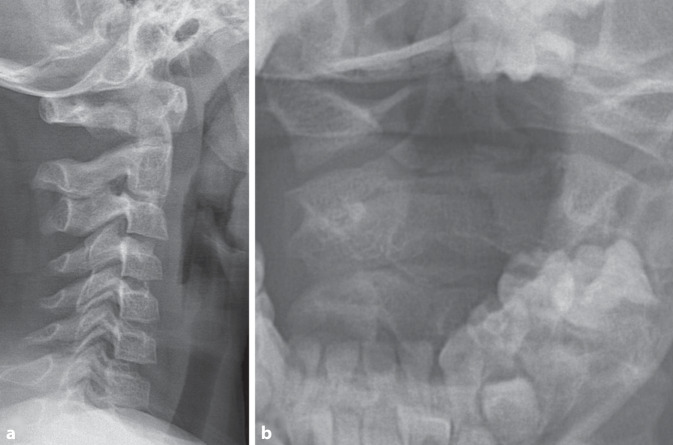

Epiphysiolysis of the dens axis is a rare injury in childhood but should be reliably investigated in the presence of typical pathological mechanisms. In our case, the injury in a four-year-old boy after a fall on his neck could not be diagnosed in the initial X‑ray. The diagnosis was made by means of an MRI scan performed during the course of the case and conservative treatment with a cervical collar was provided. The 10-year follow-up showed mild impairments, especially when remaining in a flexed position for long periods (e.g. when reading). In addition, the question arises retrospectively as to whether an additional injury to the C2/3 led to spontaneous fusion of the segment.